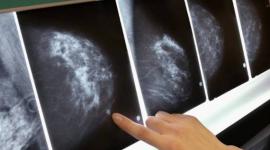

علاج يقضي على سرطان الثدي في 11 يوما